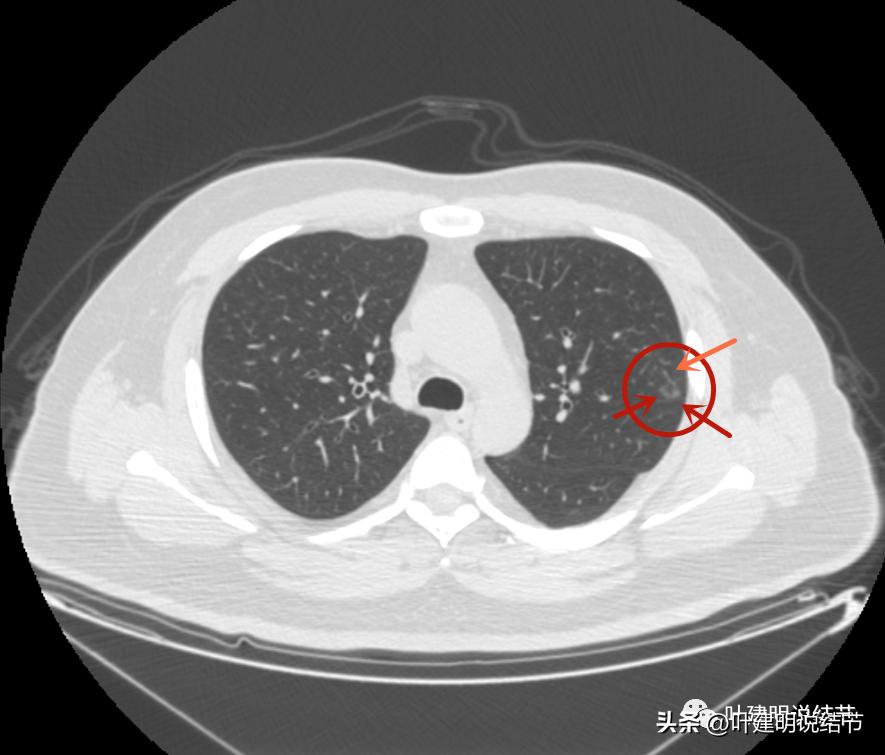

左上病灶1:磨玻璃结节,轮廓清楚伴微血管进入,中间似乎有空泡征,感觉像原位癌或不典型增生;

左上病灶2:混合磨玻璃结节,密度偏高,边缘稍糊,但轮廓相对清,有微血管分支进入,考虑微浸润性腺癌或浸润性腺癌可能大;

左上病灶3:混合磨玻璃结节偏实性,内部密度不均,整体轮廓清,有浅分叶,也有小血管关系密切,考虑浸润性腺癌可能性大;

左上病灶4:舌段磨玻璃结节,边缘显力糊,整体轮廓较清,不典型增生可能性大点。